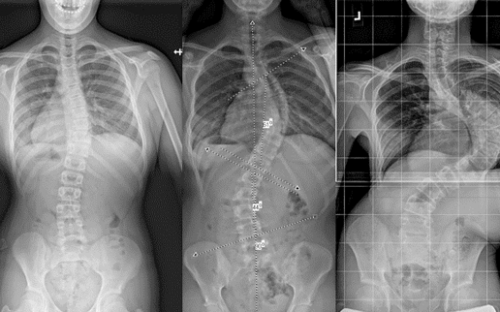

ويتم تقييم النتائج بشكل دوري من خلال الأشعة السينية لقياس زاوية الانحناء (زاوية كوب).

إذا أظهرت المتابعة أن الانحناء لم يتفاقم، فهذا يعني أن العلاج بالحزام ناجح، ويستمر حتى اكتمال النمو العظمي.

أما في الحالات التي تستمر فيها الزيادة رغم الالتزام، فقد يوصي الطبيب بخيارات علاجية أخرى.

نجاح الحزام الطبي لعلاج اعوجاج العمود الفقري عند المراهقين لا يعتمد على ارتدائه فقط، بل على تفاصيل دقيقة مثل تصحيح دوران الفقرات الأولى وسرعة هذا التصحيح. متابعة الأهل مع الطبيب، الالتزام بعدد ساعات الارتداء، واستخدام الحزام المصمم خصيصًا لكل طفل، جميعها عوامل تزيد من فعالية العلاج وتمنح الطفل فرصة أفضل لنمو ظهر مستقيم وحياة طبيعية.

التطور الكبير في تصميم الأحزمة الطبية جعل علاج اعوجاج العمود الفقري عند المراهقين أكثر نجاحًا وأقل إزعاجًا. باستخدام تقنيات التصوير الثلاثي الأبعاد والمحاكاة الرقمية، أصبح الحزام أكثر خفة وراحة، ويعطي نتائج أفضل في تصحيح الانحناء والتواء العمود الفقري.